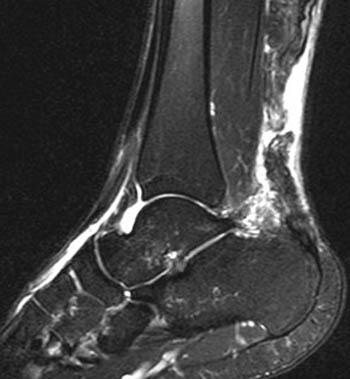

MRI musculoskeletal lower extremity tendon rupture Kuwada staging

Figure 3. Musculoskeletal MRI of the lower extremity. MRI in T2 and STIR sequences is decisive for quantifying diastasis in complete tears (Kuwada classification), assessing residual parenchymal degeneration, and planning surgical repair.

MRI is indicated in suspected complete rupture, preoperative planning, and complex insertional tendinopathy evaluation. Preferred sequences are sagittal T1, T2, and STIR. A complete tear shows tendon discontinuity with hyperintense signal in the T2/STIR gap, proximal stump retraction, and peritendinous edema. MRI provides critical surgical planning data: gap length, residual degeneration, paratenon integrity, and Haglund deformity morphology.